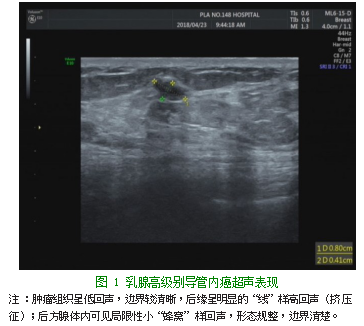

女,42岁,患者于几天前发现右侧乳腺肿物,伴轻微疼痛,无发热,无乳头凹陷、乳头溢液,无胸闷、胸痛,无咳嗽、咳痰等症状。既往曾有“右侧乳腺纤维瘤切除术、子宫肌瘤”病史。右侧乳腺彩色多普勒超声检查:乳腺外下象限8点处可见0.8 cm×0.4 cm的低回声区,形态较规整,边界较清晰,后缘呈明显的“线”样高回声(挤压征);其结节后方腺体内可见局限性小“蜂窝”样回声,形态规整,边界清楚(见图1)。

乳腺导管原位癌(Ductal Carcinoma In Situ,DCIS)是一种肿瘤性导管内病变,2003年WHO新分类法将DCIS归入癌前病变范畴,肿瘤细胞仍在基底膜内生长,周围间质无癌细胞的浸润[1];其特征是上皮细胞增生显著,细胞异型性从轻微到明显,有发展为浸润性乳腺癌的倾向,所以早期发现有重要意义。低级别DCIS和高级别DCIS在遗传学上有明显不同表现,低级别DCIS可能发展为分化较好的浸润性导管癌,而高级别DCIS可能发展为分化较差的浸润性导管癌或髓样癌[2]。导管原位癌通常有一个缓慢的发展模式,在许多病例中并没有完全发展成临床意义上的浸润性癌。中高级别的导管原位癌实施手术确实提高了生存率。然而大多数女性在这种情况下接受了积极的外科手术和放射治疗[3]。实际上本例发展明显较快,ER(-)Ki-67(+)30%增加,符合侵袭性的生物学特征[4];后者是一种与细胞周期相关的蛋白质,是检测肿瘤增殖活性最可靠的指标[5]。以往资料显示[6]高级别DCIS超声表现都为低回声,多数形态不规则,有微钙化及穿支血流信号,表现出浸润性乳腺癌的一些特征,但缺乏浸润性乳腺癌典型的毛刺征、角征。本例表现为后方增强回声边界,似有被“挤压”感,我们暂定为“挤压”征。肿块后方的小囊性表现,可能也是肿块压迫引流不畅所致导管扩张。该例肿块后方导管扩张,与Moon WK等[7]研究的75%的导管扩张一致;也与文献报道极少转移较吻合[8]。

本例特点:(1)早期由于过度生长,造成周边挤压样改变,尤以后方增强边缘明显,可能是识别的重要早期征象;(2)生长非常快,以至后方囊性扩张呈小蜂窝状;(3)阻力指数较低RI 0.58;(4)近期或短期复查,对追踪其发展变化意义重大。